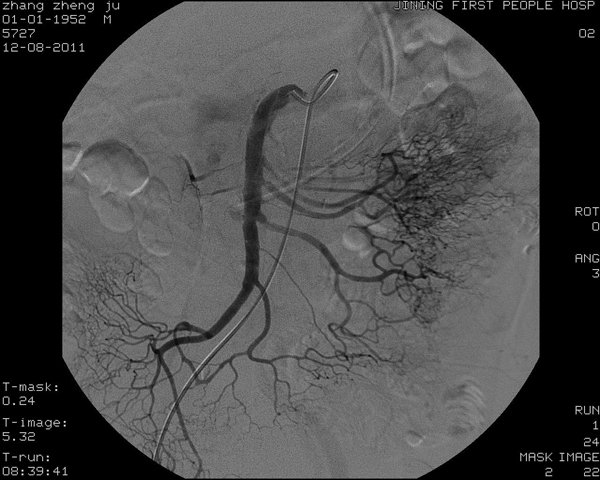

(1)肠系膜上动脉和腹主动脉之间的角度过小:十二指肠水平部位于腹膜后,从右至左横跨第三腰椎和腹主动脉,其上前方有肠系膜上动脉血管神经鞘骑跨。肠系膜上动脉一般在第一腰椎水平处分出,与腹主动脉呈50°~60°角。正常成人在十二指肠水平部前方有时可见肠系膜上动脉的压迹,如果肠系膜上动脉和腹主动脉之间的角度过小,或肠系膜上动脉从腹主动脉的分支部位过低,可压迫从中间通过的十二指肠引起梗阻症状。